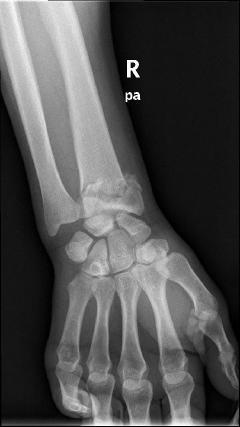

Περίπτωση 2ου ασθενούς